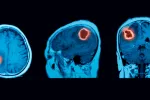

Identifican una prometedora diana terapéutica para tratar gliomas